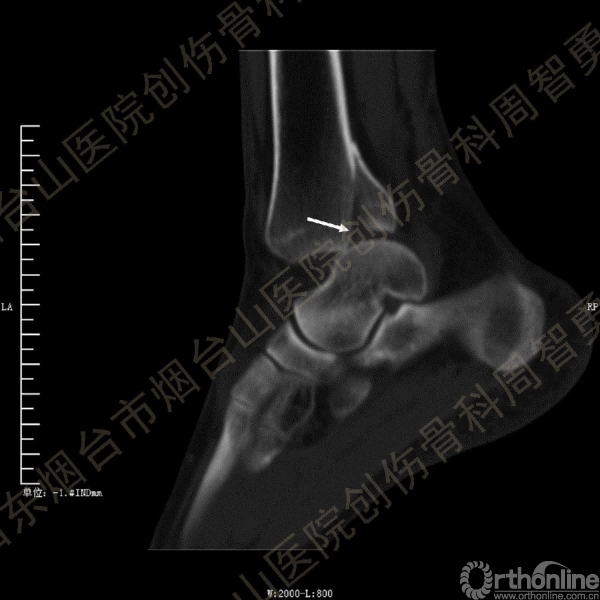

患者一般情况可,左踝关节肿胀,见皮下瘀斑,内、外、后侧有压痛,左踝关节主动运动受限,左足皮肤感觉、血供未见明显异常,左足趾各关节可主动运动。左踝关节正位X线片和CT重建示内踝内上方双层骨皮质影(图1a,c),CT示后侧骨折块分为后内侧骨折块和后外侧骨折块(图2a,b),后内侧骨折块累及内踝后丘,后丘骨折线呈冠状位(图2c),后内侧骨折块腹侧有向近端塌陷的小块骨软骨骨折块(图2d),CT也显示Chaput骨折块(图1c,2e)。

经典的后踝骨折发生于低能量旋转外力所致的踝关节骨折;标准pilon骨折见于高能量轴向暴力;而后侧pilon骨折是旋转外力和轴向暴力共同作用的结果,属于中等能量的损伤。踝关节骨折中的后踝骨折源自下胫腓后韧带的牵拉,骨折块位于后外侧,常为单一的三角形骨折块,大小从关节外片状骨折到累及胫骨远端关节面矢状径的40%(图4a)。后侧pilon骨折中的后侧骨折块较大,累及内踝后丘(三角韧带深层起点)在内的整个胫骨远端后侧,分为后内侧骨折块和后外侧骨折块,后内侧骨折块腹侧有向近端塌陷的骨软骨骨折块(图4b)。后侧pilon骨折中的内踝骨折线并不是水平位而是冠状位,可合并内踝前丘骨折。后侧pilon骨折踝关节正位X线片示特异性的内踝内上方双层骨皮质影(图1a,c)。这是由于后内侧骨折块的骨折线延伸到胫骨远端骨骺和干骺端的内侧骨皮质,其移位后的边缘成像所致。水平位CT显示后侧骨折块分为后内侧骨折块和后外侧骨折块,矢状位CT示后内侧骨折块腹侧有向近端塌陷的骨软骨骨折块。

↑图 1a

↑图 1b

图 1 术前左踝关节正侧位X线片和CT重建,箭头所示内踝内上方双层骨皮质影(a,c)